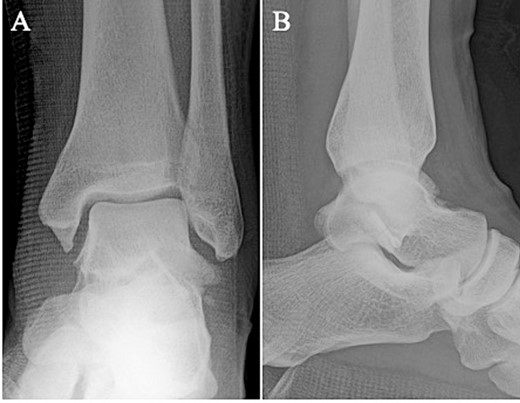

A 24-year-old male basketball player presented to our hospital complaining of left lateral ankle pain during a cutting motion. His height, weight, and body mass index were 172 cm, 64.0 kg, and 21.6 kg/m2, respectively, and he had no history of previous medical conditions. On his first visit to our hospital, he could not walk due to pain. Physical examination revealed swelling, ecchymosis, and tenderness at the lateral aspect of his left ankle. The American Orthopedic Foot and Ankle Society (AOFAS) score was 32 out of 100 points. Plain radiographs of the left ankle showed no abnormal findings in the anteroposterior view, but a fracture line was discovered at the base of the lateral process of the talus in the lateral view (Fig. 1). Non-contrast computed tomography (CT) showed a simple fracture line that extending from the talofibular articular surface down to the posterior talocalcaneal articular surface of the subtalar joint. In addition, the bone fragment was displaced >2 mm (Fig. 2). The patient was diagnosed with Type I LPFT and underwent surgical treatment.

Plain radiographs of the left ankle showed no abnormal findings in the anteroposterior (A) view, but a fracture line was discovered at the base of the lateral process of the talus in the lateral (B) view.